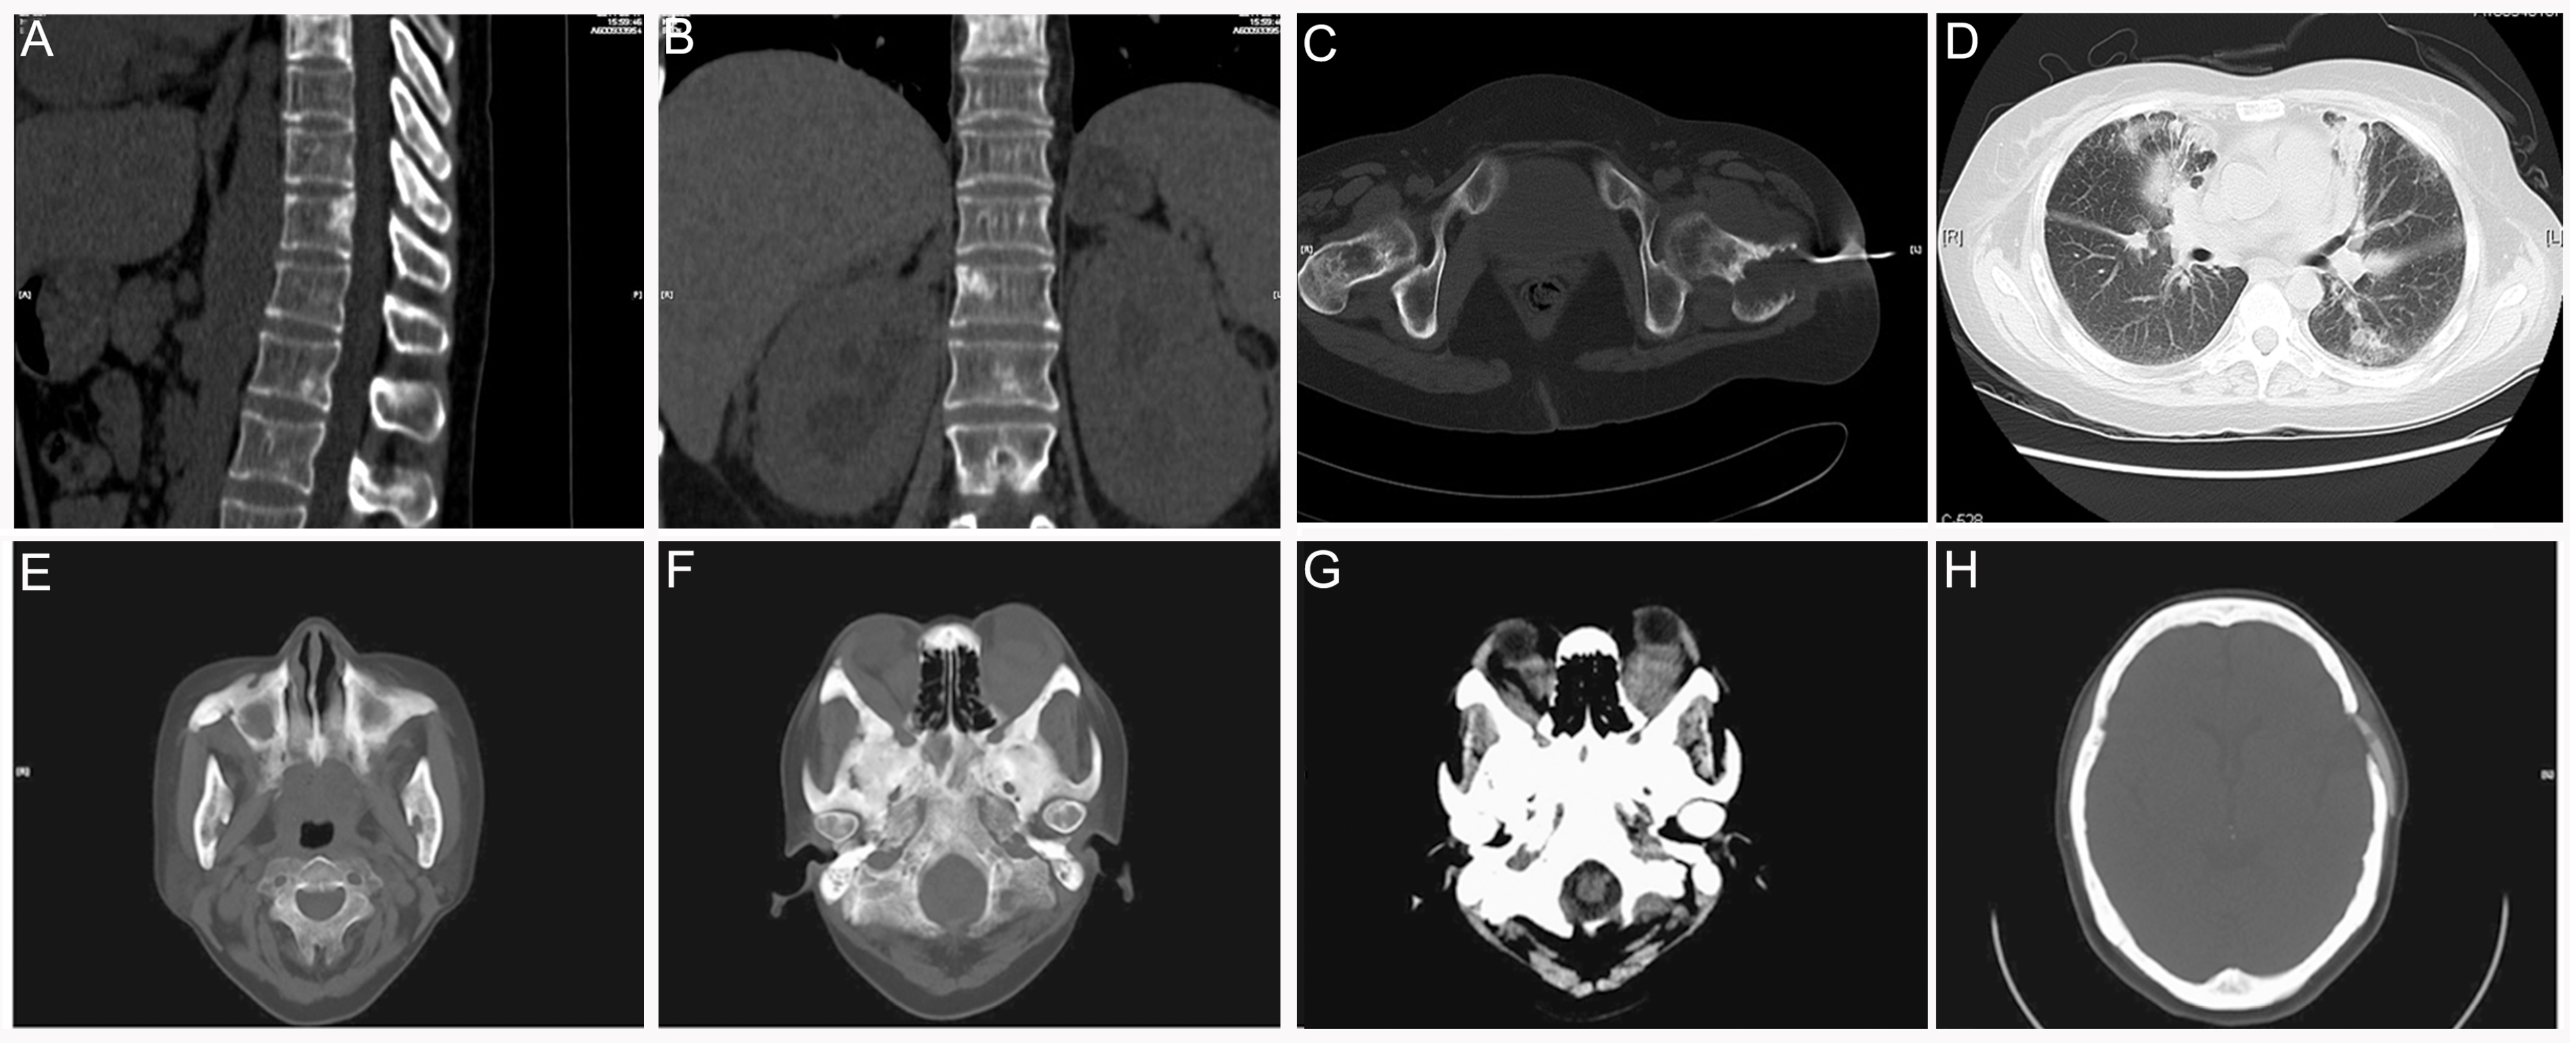

3.5. Erdheim–Chester Disease (ECD)

3.6. Langerhans Cell Sarcoma